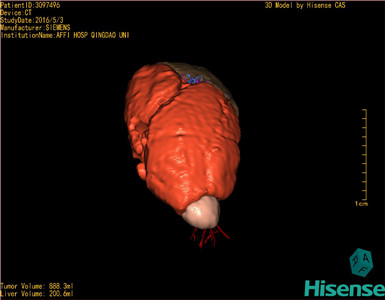

将0.625mm双源薄层CT资料的静脉期和动脉期Dicom格式文件导入海信CAS系统。

通过调节窗宽窗位调整CT序号,对肿瘤,肝实质,胆囊,下腔静脉,肿瘤,肝动脉、门静脉及肝静脉等进行三维重建;系统自动计算肿瘤体积和肝脏体积。(模拟手术操作,自动计算切除肿瘤体积。

术前三维重建:

重建图片